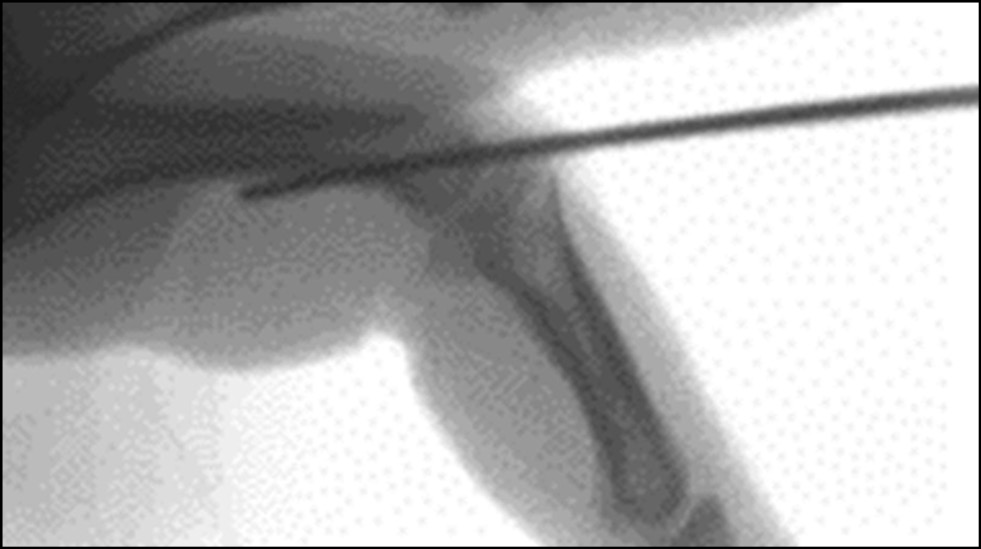

Ограничение гиперэкстензии спицами

Чтобы избежать громоздкой шины и устранить опасения по поводу соблюдения правил использования шины, была представлена техника блокирующей спицы (рис. 12). Первоначально Sugawa описал эту технику в 1979 году, исходя из принципа, что блокирующая спица предотвращает компрессионную нагрузку на ладонный край основания средней фаланги. Это не только предотвратило повторный дорсальный подвывих или вывих, но и устранило необходимость в постоянной фиксации перелома или костного трансплантата для исключения повторного смещения [17]. Данный метод состоит в закрытой репозиции и транскутанном трансартикулярном проведении спицы через головку проксимальной фаланги так, что исключается разгибание в суставе в крайние 30–60° [21], что повторяет принцип ортезирования.

Рис. 12. Интрамедуллярная блокирующая спица [5].

Fig. 12. Intramedullary blocking spoke [5].